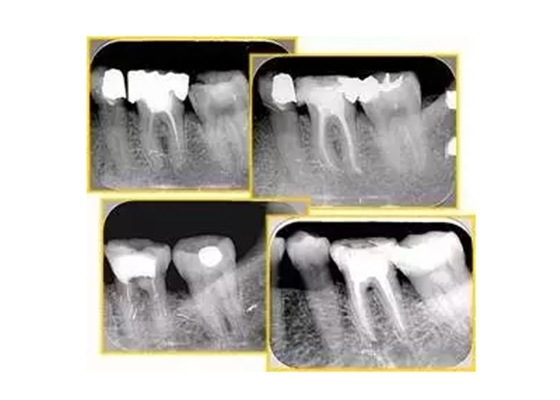

左圖為根管充填術(shù)后 X 線片。圖中可見,根管充填較好。右下圖有白色小點(diǎn),為側(cè)方加壓導(dǎo)致糊劑擠出所致,表明根管充填比較致密。

致密、恰到好處的充填可去除干凈根管里感染灶,機(jī)體逐漸恢復(fù)。

多根牙時(shí)候需進(jìn)行偏移投照,正位投照無法說明具體哪根牙根管充填效果。 二、根管預(yù)備及充填要求